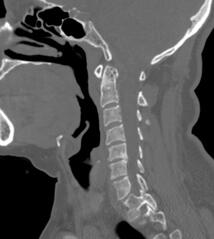

Application of self-locking cages in the treatment of cervical spinal stenosis: 2-year follow-up results.2. Levels of Cytokines and MicroRNAs in Individuals with Asymptomatic Hyperuricemia and Ultrasonographic Findings of Gout: A Bench-to-Bedside Approach. Arthritis Care Res (Hoboken). 2018 Dec;70(12):1814-1821.3. Hyperuricemia on Admission Predicts Short-Term Mortality due to Myocardial Infarction in a Population with High Prevalence of Cardiovascular Risk Factors. Rev Invest Clin. 2017 Sep-Oct;69(5):247-253.4. The Type of Trypanosoma Cruzi Strain (Native or Non-Native) Used as Substrate for Immunoassays Influences the Ability of Screening Asymptomatic Blood Donors. Rev Invest Clin. 2016 Nov-Dec;68(6):286-291.5. Glucose and glutamine metabolism control by APC and SCF during the G1-to-S phase transition of the cell cycle. Journal of Physiology and Biochemistry. 2014;70(2):569-81.

Conducto cervical estrecho